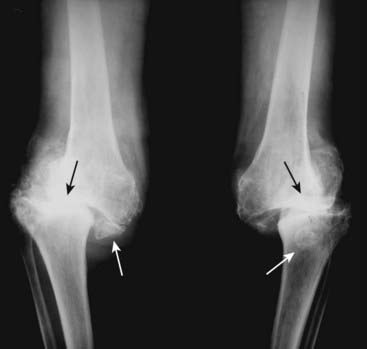

Figure 23-9 Charcot arthropathy of knees.

As a hypertrophic arthritis, a Charcot joint will demonstrate extensive subchondral sclerosis. The hallmark findings of a Charcot joint, however, are fragmentation of the bones surrounding the joint, which produces numerous small, bony densities within the joint capsule (solid white arrows) as well as joint space destruction (solid black arrows). The most common cause of a Charcot joint of the knee is diabetes.